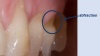

Abfraction

An abfraction is a splintering of the tooth at the enamel-cementum border (usually just below the gum line).

As you can see from the photos abfractions are accompanied by gum recession so that the softer, cementum, part of the tooth is exposed, accelerating decay.